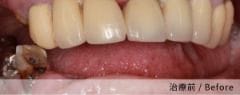

實際案例分享

案例一